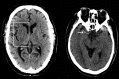

Standard imaging in acute stroke is undertaken with the aim of diagnosing the underlying cause and excluding stroke mimics. In the presence of ischaemic stroke, imaging is also needed to assess patient suitability for treatment with intravenous thrombolysis. Non-contrast CT is predominantly used, but MRI can also exclude any contraindications to thrombolysis treatment. Advanced stroke imaging such as CT and MR angiography and perfusion imaging are increasingly used in an acute setting. In this review, we discuss the evidence for the application of these advanced techniques in the imaging of acute stroke.